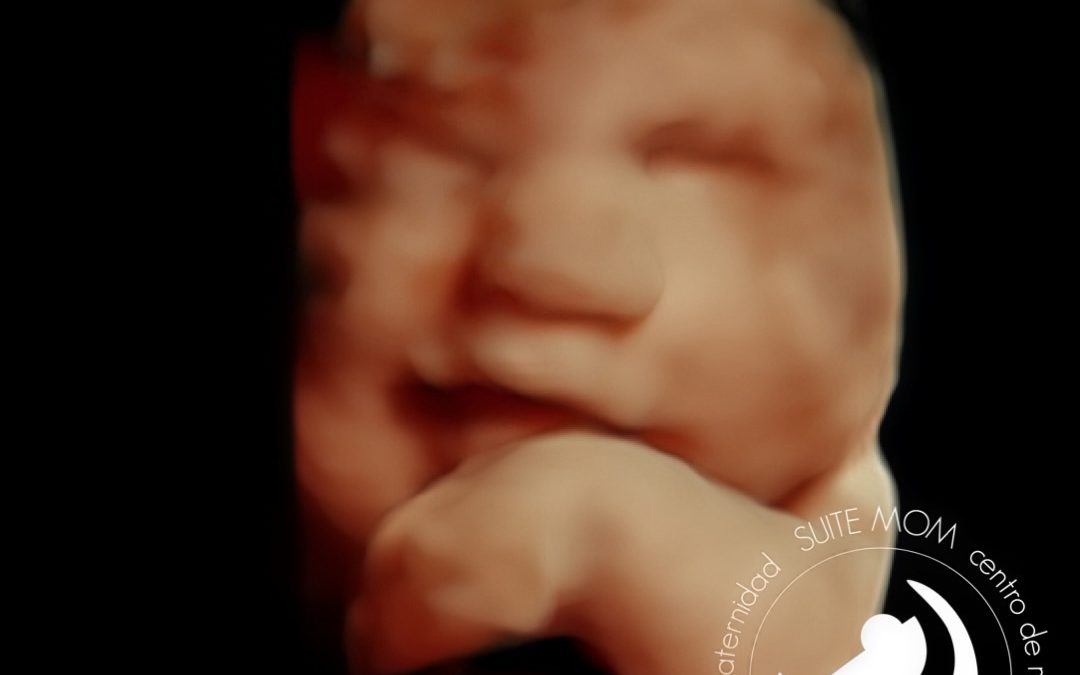

Ecografía emocional 5D. 33 semanas de gestación.

Ecografía emocional 5D, Bebé de 33 semanas de embarazo. Realizada en nuestro centro de Maternidad, Suite Mom. San Fernando de Henares, Madrid.

En esta ecografía podemos ver a un bebé de 33 semanas de gestación. Nos está sonriendo!! Tiene su brazo izquierdo cerca de la carita, y la manita doblada frente a su barbilla.